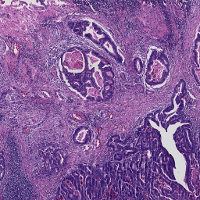

A dataset of colorectal cancer images and patches from 10 patients was recently made publicly available [4]. The test dataset consists of two subsets. The first subset contains 5000 patches of 150150 pixel extracted from 10 H&E slides of CRC cases. The patches contain 625 examples of 8 tissue types, namely (i) tumor epithelium, (ii) simple stroma, (iii) complex stroma, (iv) immune cell conglomerates, (v) debris and mucus, (vi) mucosal glands, (vii) adipose tissue, (viii) background. We name this subset as CRCp. The second subset contains 10 tiles of size 50005000 pixel of H&E stained CRC tissue samples, which we call CRCt.

Stain normalization (SN) involves transforming an image into another image , through the operation , where is a set of parameters extracted from a predefined template image and is the mapping function that matches the visual appearance of a given image to the template image. The parameters are generally defined to capture color information of the main stain components in the image (e.g. H and E). As a result, stain-normalized images will have a distribution of colors that resemble the ones of the template. In Figure 1, images from CRCt and their stain-normalized version based on the WSI template of Figure 2 are depicted.

The definition of classes in our RC data is slightly different from the one coming with the CRC dataset. Therefore, we grouped corresponding classes as described in Table 2, which resulted in a 6-class problem, used to evaluate the performance of the trained ConvNet applied to CRC data. Applying the ConvNet directly to CRC data gave a poor accuracy value of 50.96% (experiment A). Based on this result, we investigated the role of staining in this classification task. For this purpose, we selected a representative RC image from the RC cohort as the template image to define the mapping parameters for the SN1 and SN2 algorithms999The function for SN1 is available in the form of look-up table at https://github.com/francescociompi/stain-normalization-isbi-2017. Successively, we stain-normalized patches in the CRC dataset and classified it again with the same ConvNet. Stain normalization allowed to remarkably improve the accuracy by more than 20%, reaching values of 75.55% (experiment B) and 73.99% accuracy for SN1 and SN2 respectively. Besides the difference in accuracy, we found that SN2 failed to normalize 3 patches of adipose tissue, and it tends to force color normalization regardless of the type of tissue considered. As an example, in Figure 4, two CRC patches are depicted, containing tumor and blood cells respectively. While both SN1 and SN2 correctly normalize stain for the tumor patch, the characteristic red color of blood cells is completely lost using SN2, while SN1 keeps a substantial component of the red channel.